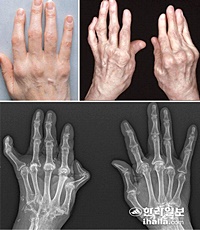

류마티스 관절염(RA)은 신체 전체에 관절통과 손상을 유발할 수 있는 자가 면역 질환입니다. 이 질환은 보통 신체 양쪽에서 동일한 관절에 영향을 주기 때문에, 한쪽 팔이나 다리의 관절이 영향을 받으면 반대쪽도 동일한 영향을 받을 수 있습니다. 이러한 특징은 의사들이 류마티스 관절염을 다른 형태의 관절염과 구별하는 데 도움이 됩니다.

조기에 진단할수록 치료 효과가 크기 때문에, 류마티스 관절염의 초기 증상을 알고 있는 것이 매우 중요합니다. 이 질환은 활막이 존재하는 모든 관절에서 발생할 수 있으며, 자가면역 이상으로 인해 외부 공격으로부터 신체를 보호하는 면역체계가 오작동하게 됩니다. 우리나라에서는 전체 인구의 약 1%가 류마티스 관절염을 앓고 있는 것으로 알려져 있습니다. 초기 증상은 눈에 잘 띄지 않으며, 통증과 뼈마디 변형이 발생한 후에야 발견될 수 있습니다.

류마티스 관절염이 발생하면 손과 발의 관절 주변 피부가 붉어지고 부어오를 수 있습니다. 이러한 관절의 홍조와 붓기는 시각적으로 확인할 수 있는 초기 증상입니다. 부어오른 관절이 며칠 동안 지속되거나 치료가 필요할 정도로 악화될 수 있으므로, 빠르게 진단을 받고 치료를 받는 것이 중요합니다.